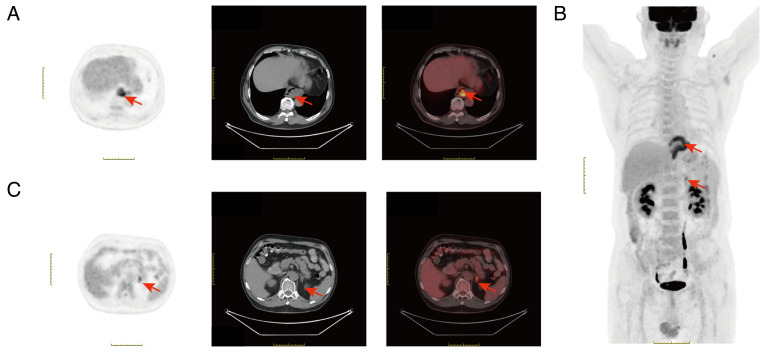

平滑肌瘤是一种良性肌肉异常,通常发生在食管中部和远端三分之一处,导致食管壁增厚和随后的食管管腔狭窄。值得注意的是,食管平滑肌瘤在正电子发射断层扫描(PET)上通常没有显示18f -氟脱氧葡萄糖(FDG)摄取增加。本文报告1例食管平滑肌瘤合并肾上腺腺瘤。pet计算机断层扫描结果显示,食道下段和左肾上腺的FDG代谢增加,最大标准化摄取值分别为6.5和4.1。因此,患者最初被诊断为食管恶性肿瘤并左肾上腺转移。开放手术完全切除病变,常规病理分析结果为食管平滑肌瘤合并肾上腺皮质腺瘤。本研究提示,为了避免不必要的手术,食管平滑肌瘤和肾上腺皮质腺瘤的诊断应通过内镜、内镜超声、计算机断层扫描、磁共振成像和组织样本病理等综合评估,而不仅仅是PET。

Leiomyoma is a benign muscular abnormality that commonly occurs in the middle and distal third of the esophagus, leading to thickening of the esophageal wall and subsequent esophageal luminal narrowing. Notably, esophageal leiomyoma often does not show increased 18F-fluorodeoxyglucose (FDG) uptake on positron emission tomography (PET). The present study described a case of esophageal leiomyoma combined with adrenal adenoma. Results of the PET-computed tomography analysis revealed that FDG metabolism was increased in the lower segment of the esophagus and the left adrenal gland, with maximum standardized uptake values of 6.5 and 4.1, respectively. Therefore, initially, the patient was diagnosed with an esophageal malignant tumor with left adrenal metastasis. Open surgery was performed for complete removal of the lesions, and results of a routine pathological analysis revealed esophageal leiomyoma combined with adrenal cortical adenoma. The present study indicates that to avoid unnecessary surgeries, esophageal leiomyoma and adrenal cortical adenoma should be diagnosed through a comprehensive assessment with endoscopy, endoscopic ultrasound, computed tomography, magnetic resonance imaging and tissue sample pathology, not just PET.